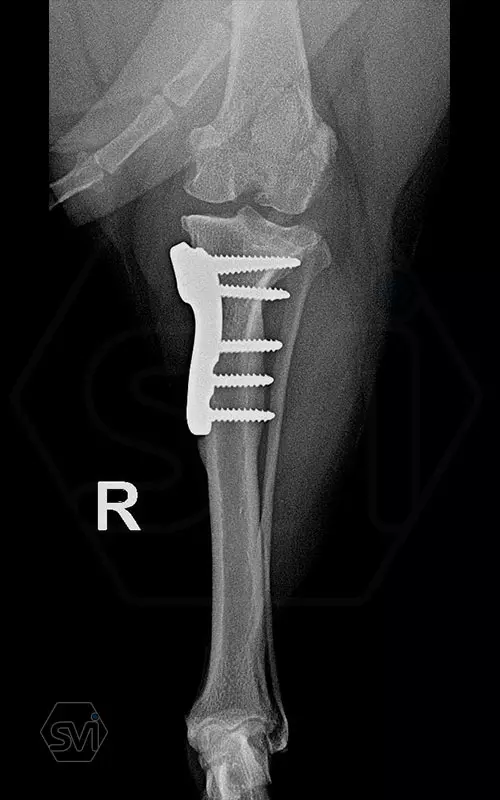

The cranial cruciate ligament rupture of a 7-year-old 8 kg active mix dog was solved a year ago with a precontured polyaxial 2.4mm system, now the other leg has been laid out, and this plate was used here as well. The stability of the system, its fit to the bone and the good healing can be measured nicely on the 1-year control X-ray.

The 2.4 system is great to use where the 2.0mm is already small, but the 2.7mm is still very big. This is a populous family of 6-14 kg dogs, according to our own data for 2021, the 2.4 mm size makes up 14% of all TPLO surgeries!